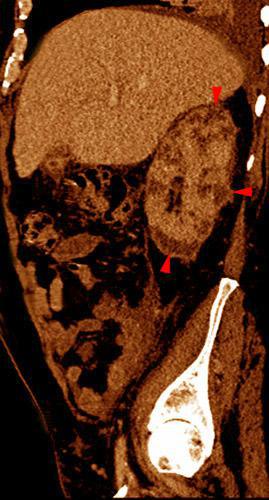

Abscesos renales en pionefrosis

VR seccional. Visión sagital izquierda. Nefromegalia. Múltiples lesiones hipodensas (puntas de flecha) correspondientes a abscesos renales